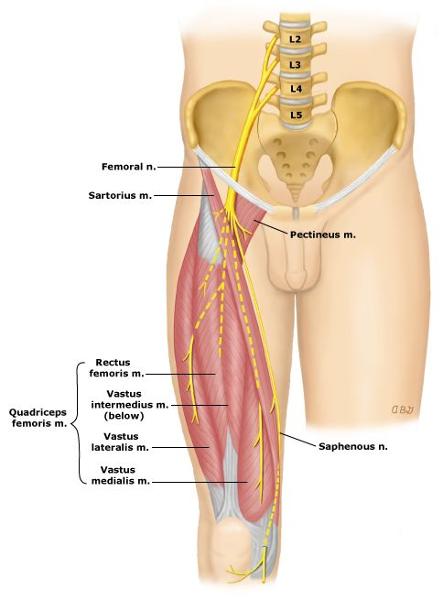

The femoral nerve is formed from ventral rami of spinal cord levels ___________

L2-L4

What is the path of the femoral nerve?

located superficial to iliacus

runs deep to inguinal ligament to enter anterior thigh

most lateral content of the femoral triangle

Which muscles are innervated by the femoral nerve?

all muscles of anterior thigh: sartorius, rectus femoris, vastus lateralis, vastus medialis, vastus intermedius

the iliacus

and half of pectinius

origin course and distribution of saphenous nerve

spinal cord level

O femoral nerve

C descends with femoral vessels through femoral triangle and adductor canal then descends with great saphenous vein

D supplies skin on medial side of leg and foot

L3-L4

origin and distribution of femoral nerve

O L2-L4

D iliacus, flexors of the hip and extensors of the knee